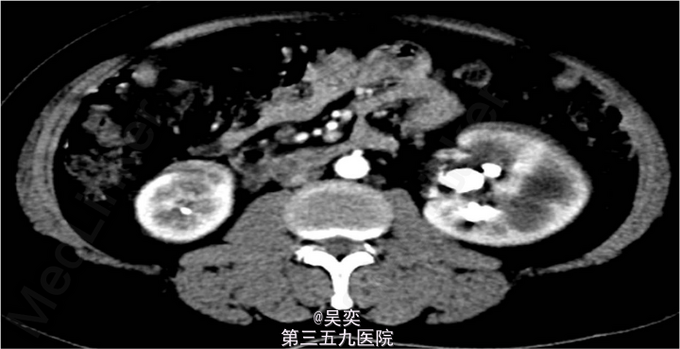

3、查体:无阳性体征 4、辅助检查:我院泌尿系B超:右输尿管上段结石并上段扩张,双肾多发结石。入院后白细胞总数10.550x10E9/L,中性粒细胞绝对值6.970x10E9/L。尿常规:白细胞计数50.30个/ul,红细胞计数145.70个/ul。生化全套:谷丙转氨酶75.000U/L,谷草转氨酶44.000U/L。双肾CTU:1、左肾盂和中下盏铸型结石较前稍增多,左肾中度积水。2、右肾多发结石,右肾中度积水,右侧输尿管上段炎症。3、左肾上极巨大囊性病变较前增大,考虑扩张的肾盏,内有结石。4、盆腔多发静脉石。5、前列腺小钙化灶。其余术前常规抽血结果无特殊。

5、诊断:肾积水伴输尿管结石,肾结石,精神分裂症 6、入院后完善相关检查,心电图、胸片未见异常,CT示:1、左肾盂和中下盏铸型结石较前稍增多,左肾中度积水。2、右肾多发结石,右肾中度积水,右侧输尿管上段炎症。3、左肾上极巨大囊性病变较前增大,考虑扩张的肾盏,内有结石,排除手术禁忌症,经术前准备,于左侧经皮肾镜碎石取石术,手术顺利,术后恢复较好。